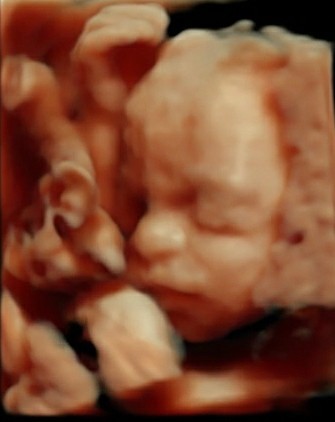

Kellyd79 · 05/08/2021 13:12

@MumOfMiracles aww she's beautiful I'm pleased it's all going well. Considering my girl has edwards she's doing well, she has an exomphalos and a small vsd but other than that it's all good. Makes me glad I decided to continue 😌

Here's my fighter

Oh my goodness! She looks so precious! I hear you too, feels such a shock to be asked if you want to terminate your pregnancy, triggers all sorts of fears. So glad our girlie's are growing and going strong! Fighter for sure. Looks like your girl is so content and snuggly in there, bless her. Rooting for both our beautiful girls as we count down our last weeks. xx

Wow! Those pictures are fantastic @kellyd79 and @MumOfMiracles! They are so clear. It is amazing. I hope you are both doing OK.

She looks beautiful . Glad to hear you’ve found the groups, hopefully you’ve seen all the survivors.